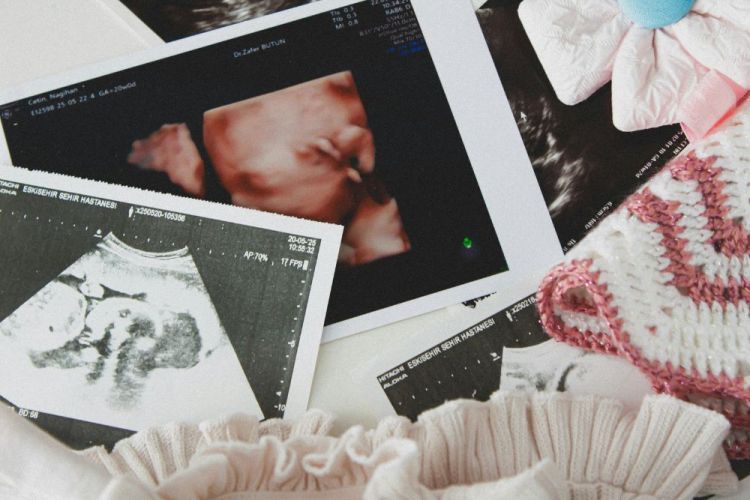

Di recente è stata aggiornata la terza parte delle linee guida sulla gravidanza fisiologica, con particolare attenzione alla diagnostica del primo e del secondo trimestre per l’individuazione di eventuali anomalie cromosomiche fetali. Si tratta di indicazioni importanti, che incidono in modo significativo sul percorso di assistenza e sulle scelte che accompagnano la gravidanza.

La terza parte degli aggiornamenti si concentra sulla diagnosi prenatale, in particolare sugli screening per le anomalie cromosomiche (come trisomie 21 della sindrome di Down, 18 della sindrome di Edwards e 13 della sindrome di Pateau). Qui il cambiamento è significativo, soprattutto nel modo in cui questi strumenti vengono proposti alle donne.

Le linee guida attuali prevedono che tutte le donne, indipendentemente dall’età, vengano informate sulla possibilità di effettuare test di screening come il test combinato (tra 11+0 e 13+6 settimane) o il test del DNA fetale su sangue materno. Non si tratta di esami obbligatori, ma di opzioni che devono essere offerte attraverso un counselling chiaro e completo, per permettere una scelta consapevole.

- Un’ecografia nel primo trimestre (entro 13+6 settimane), utile per datazione, vitalità e primo inquadramento;

- Un’ecografia morfologica nel secondo trimestre (tra 19 e 21 settimane), fondamentale per lo studio dell’anatomia fetale.